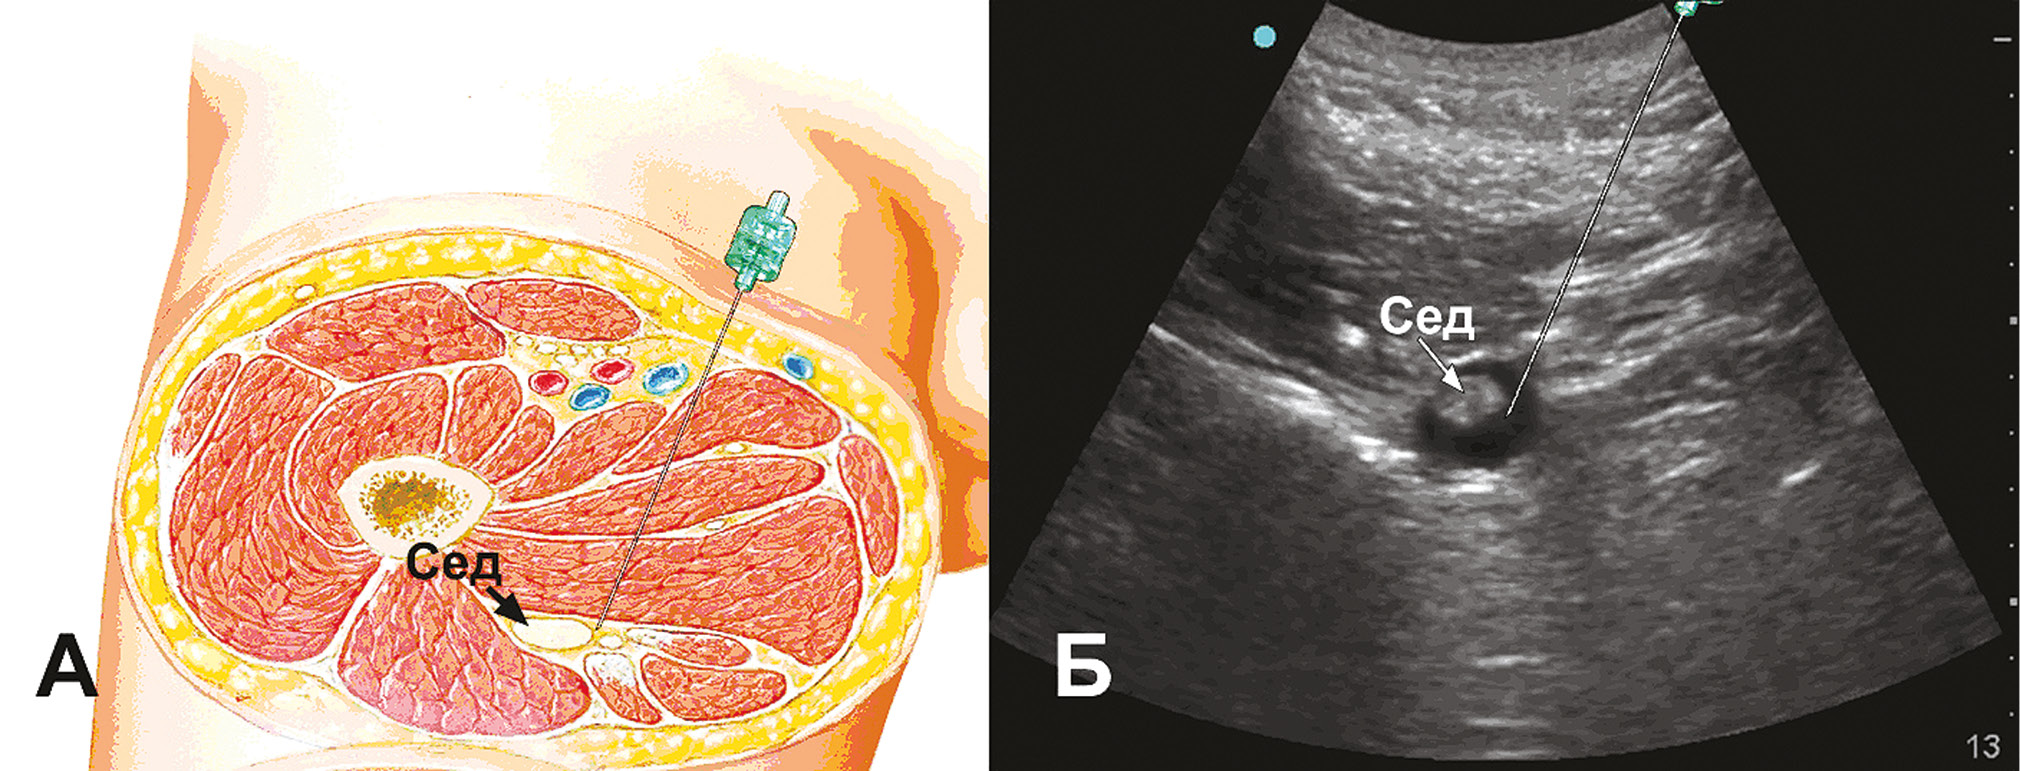

Катетеризировали одну из вен предплечья и начинали инфузионную терапию. В условиях седации 5 мг диазепама внутривенно выполняли блокаду седалищного нерва переднемедиальным доступом с использованием ультразвуковой навигации. Под визуальным контролем расположения кончика иглы, распределения МА, контролем давления во время введения, регулярными аспирационными пробами каждые 3–5 мл вводили 15 мл 0,5% раствора левобупивакаина (рис. 1). На рисунке 1 представлена схема (А) и ультразвуковая картинка (Б) блокады седалищного нерва. Седалищный нерв (рис. 1, Б) окружён раствором местного анестетика (тёмное кольцо вокруг седалищного нерва).

Рис. 1. Блокада седалищного нерва переднемедиальным доступом. А – схема блокады. Б – сонограмма блокады (Сед – седалищный нерв)

Fig. 1. Sciatic nerve block by anteromedial access. A – scheme of the blockade. Б – Sonogram of the blockade (Сед – sciatic nerve)